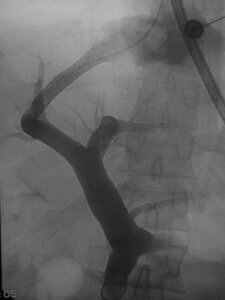

This is an image of the portal venous system after a TIPS has been created. The image shows the main portal vein dividing into the right and left portal vein as it enters the liver. It then shows a stent (the wire tubing) extending from the right portal vein into the right hepatic vein – this stent provides a new pathway for blood flow through the liver.